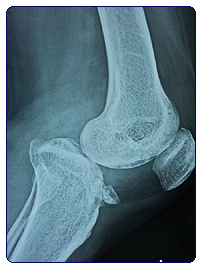

Case 1: This 30 year old lady was referred to us from Bihar (700 Km away). She sustained a complex fracture of knee – fracture of upper tibia with dislocation of the knee. The seriousness of the injury could not be comprehended by the first treating surgeon, and she was treated in plaster cast. After removal of the plaster, she realized that she could not walk. X-ray showed that her knee was subluxated. This happened because the injury was a combination of fracture plus ligament injury.

We took her up for surgery which involved 4 hours of operation. She had to be opened up from back of the knee and also from front. Ultimately the knee was put in proper shape. It took her 6 months to get back on her feet. Today she walks like a normal person.

This is a rather uncommon complex knee injury. We have recently reported this injury in Journal of Indian Orthopaedic Association.